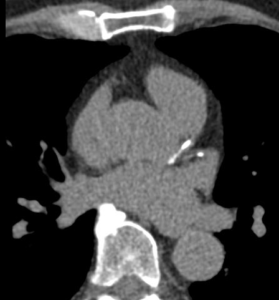

Calcium scoring is a quick, low-radiation CT scan that detects calcified plaque. It can be useful for refining risk in asymptomatic patients or those with atypical symptoms. A calcium score of zero is reassuring in many people, but it does not exclude non-calcified plaque.

Calcium Score Scan (without contrast) showing calcified plaque in the main coronary vessel (LAD). The degree of narrowing (stenosis) cannot be ascertained from this scan without contrast injection, however a risk calculation can be made based on the total amount of calcium adjusted for age and sex.